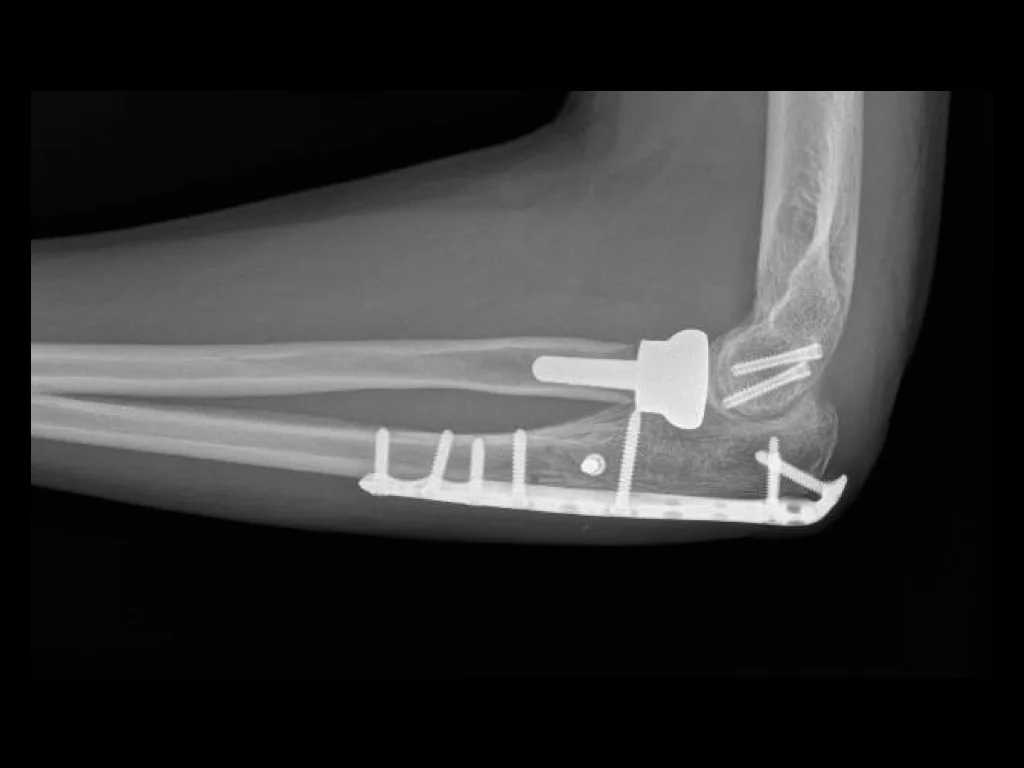

Comprehensive Orthopaedic Hand Surgery practice in Chicago's North Shore.